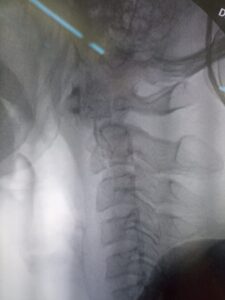

نجح فريق جراحة المخ والأعصاب بالمستشفى في إجراء عملية نادرة ومعقدة أنقذت شابًا كان يعاني من ألم شديد بالرقبة وفقدان القدرة على الحركة، نتيجة كسر بالفقرات العنقية، مع كسر بالناتئ الفقري للفقرة العنقية الثانية، مما تسبب في ضغط على الحبل الشوكي.